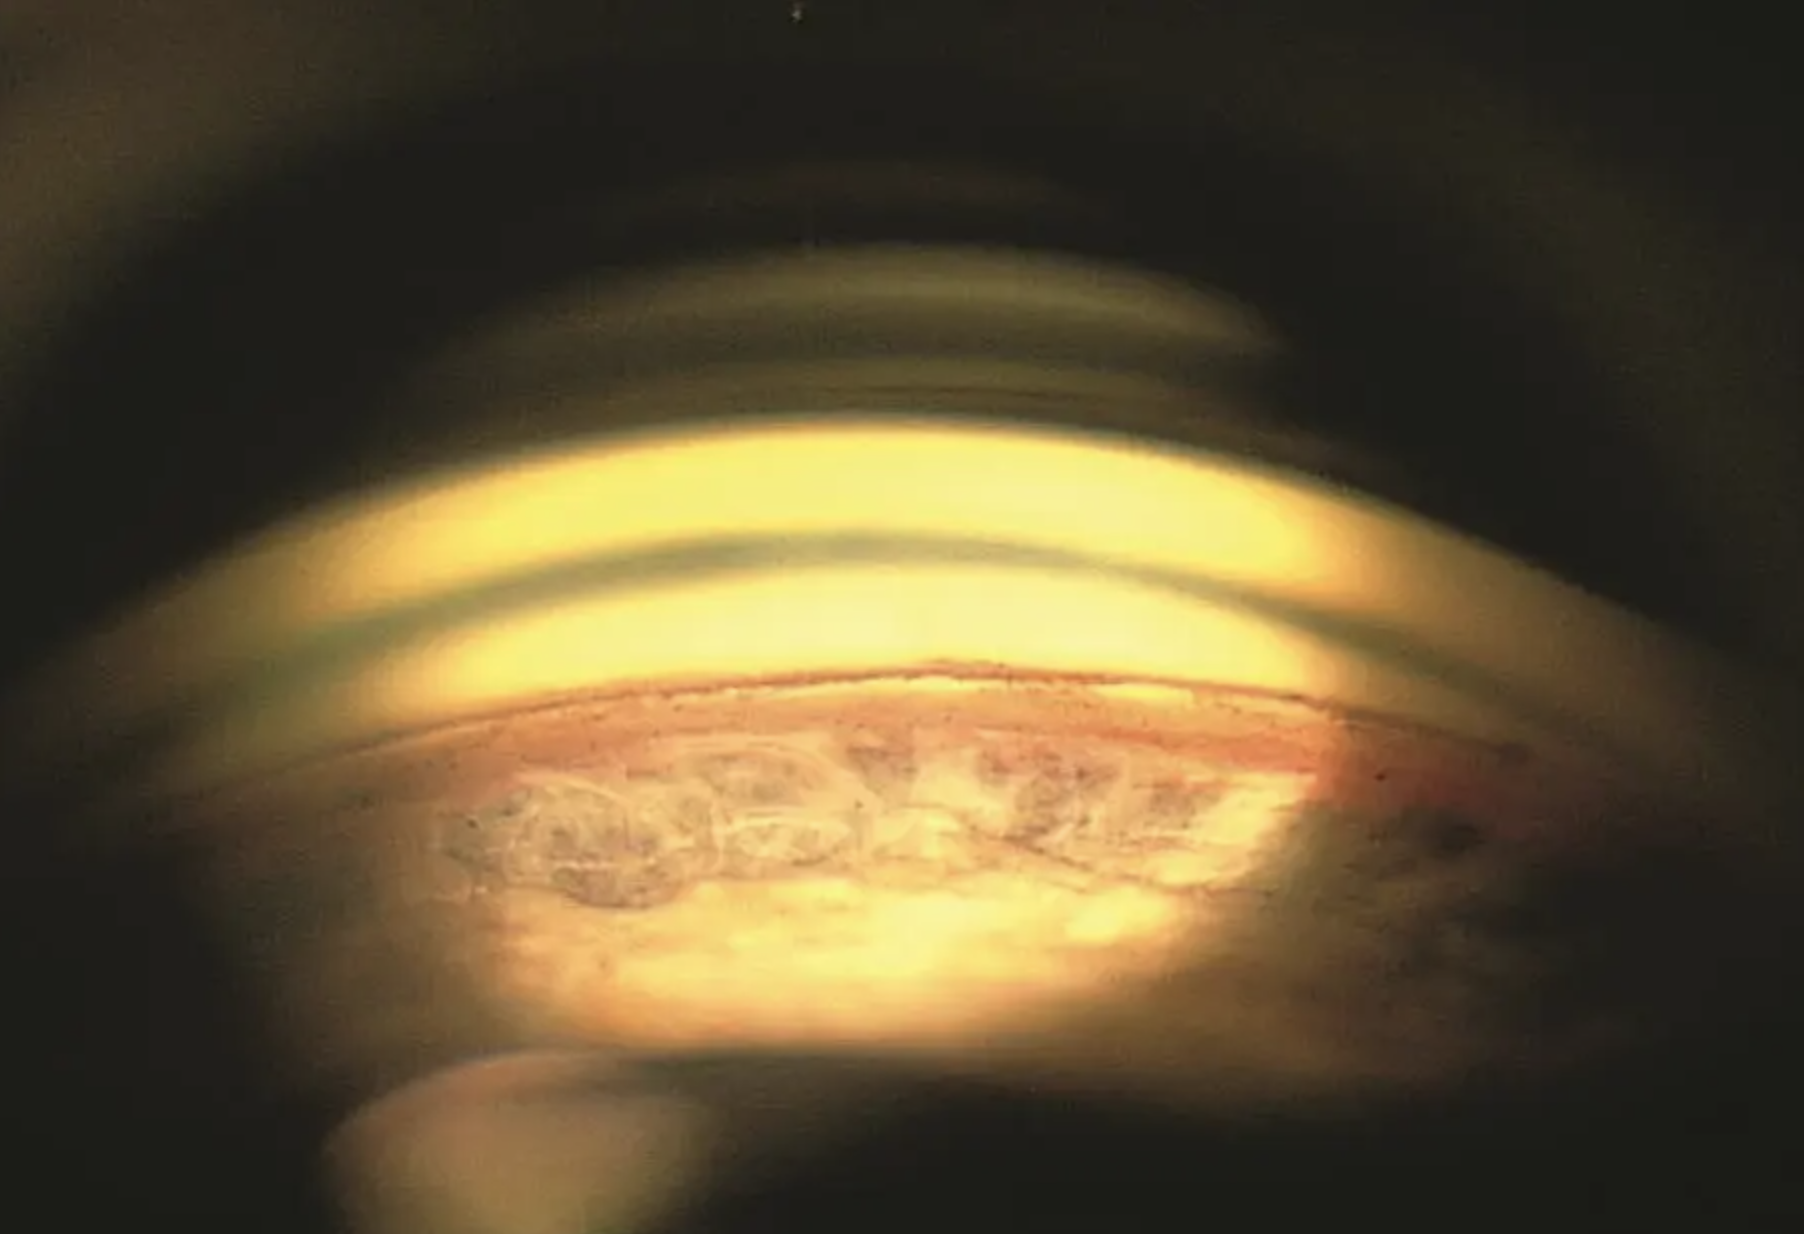

Gonio